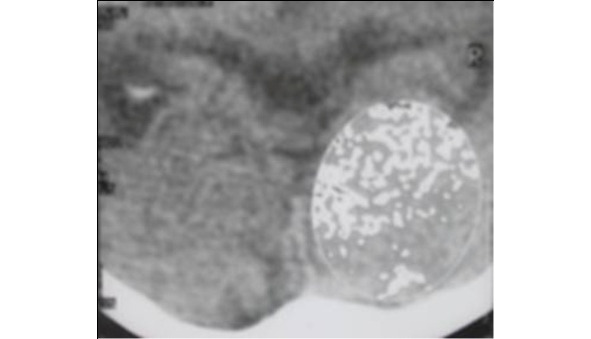

Человек рождается с анатомически сформированным головным и спинным мозгом, в котором количество нервных клеток составляет ~ 100 млрд. Мозг при рождении весит не более 100 г, а в зрелом возрасте ГМ составляет 1,5—2 кг, но количество клеток в нем не увеличивается, а к старости только уменьшается. Нервные клетки (нейроны) лишь увеличиваются в размере и удлиняют аксоны, которые достигают длины до 1—1,5 м. Сущность предложенной концепции заключается в биологическом феномене ограничения продолжительности жизни человека в зависимости от возрастного или болезнетворного накопления объема морфофункциональных повреждений, полученных его мозгом в период онтогенеза (жизни после рождения). Причиной этих молекулярно-биологических повреждений могут быть как эндогенные, так и экзогенные факторы окружающей среды, климата и профессиональных вредностей, приводящие к патогенетическим процессам в клетках нервной ткани. Невозможность или, точнее, резко ограниченная возможность самообновления клеток и низкий потенциал регенерации для реставрации поврежденной нервной ткани ГМ и СМ человека в процессе постнатального онтогенеза приводят к возрастзависимой дегенерации и атрофии нейронов, которые и формируют нарушения гомеостаза и блокирование биологических механизмов саногенеза органов и тканей организма и, несомненно, являются фундаментальными причинами сокращения продолжительности жизни. Степень выраженности молекулярно-биологического повреждения нервной ткани ГМ и СМ прямо пропорциональна продолжительности жизни человека. Нервные и психические болезни, в исходе которых лежит формирование органического морфологического дефекта нервной ткани, являются фундаментальной биологической и биофизической основой сокращения продолжительности жизни почти для всех болезней цивилизации. Именно морфологические дефекты нервной ткани ГМ и СМ сегодня легко объективизировать при помощи стандартной компьютерной томографии (КТ), так что легко выявить объем повреждения путем проведения денситометрии (программы компьютерного анализа изучения плотности ткани) КТ нервной ткани и рассчитать объем ишемизированной ткани ГМ, который соответствует диапазону плотности нервной ткани от 10 до 15 хаунсфилдов.

Рис. 1. Компьютерная томография головного мозга пациента К., 46 лет. Денситометрический анализ нервной ткани правой затылочной доли

головного мозга на выявление очагов ишемии (от 5 до 14 H) для оценки объема повреждений мозга